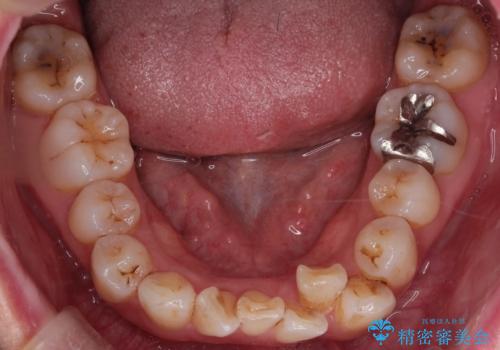

- 「歯のガタつきが気になる」「前歯の真ん中がずれている」との主訴で来院されました。診察の結果、上下の歯列に中等度の叢生(凸凹)があり、特に前歯の位置のずれ(正中の偏位)が目立つ状態でした。見た目だけでなく、かみ合わせにも影響を与える可能性があるため、全体的なバランスの改善が必要と診断しました。

治療はインビザラインを使用し、1~2週間ごとに新しいマウスピースに交換しながら段階的に歯を移動させていきました。特に上下の正中が揃うよう、奥歯や前歯の位置関係に注意を払いながら細かく設計を調整。途中の確認でも、左右のバランスが取れてきたことをご本人も実感されていました。

治療期間は約1年半で、ガタついていた歯列はきれいに整い、上下の前歯の真ん中もぴったりと揃えることができました。透明なマウスピースのため周囲に気づかれず治療が進み、快適に続けられたとの感想もいただいています。